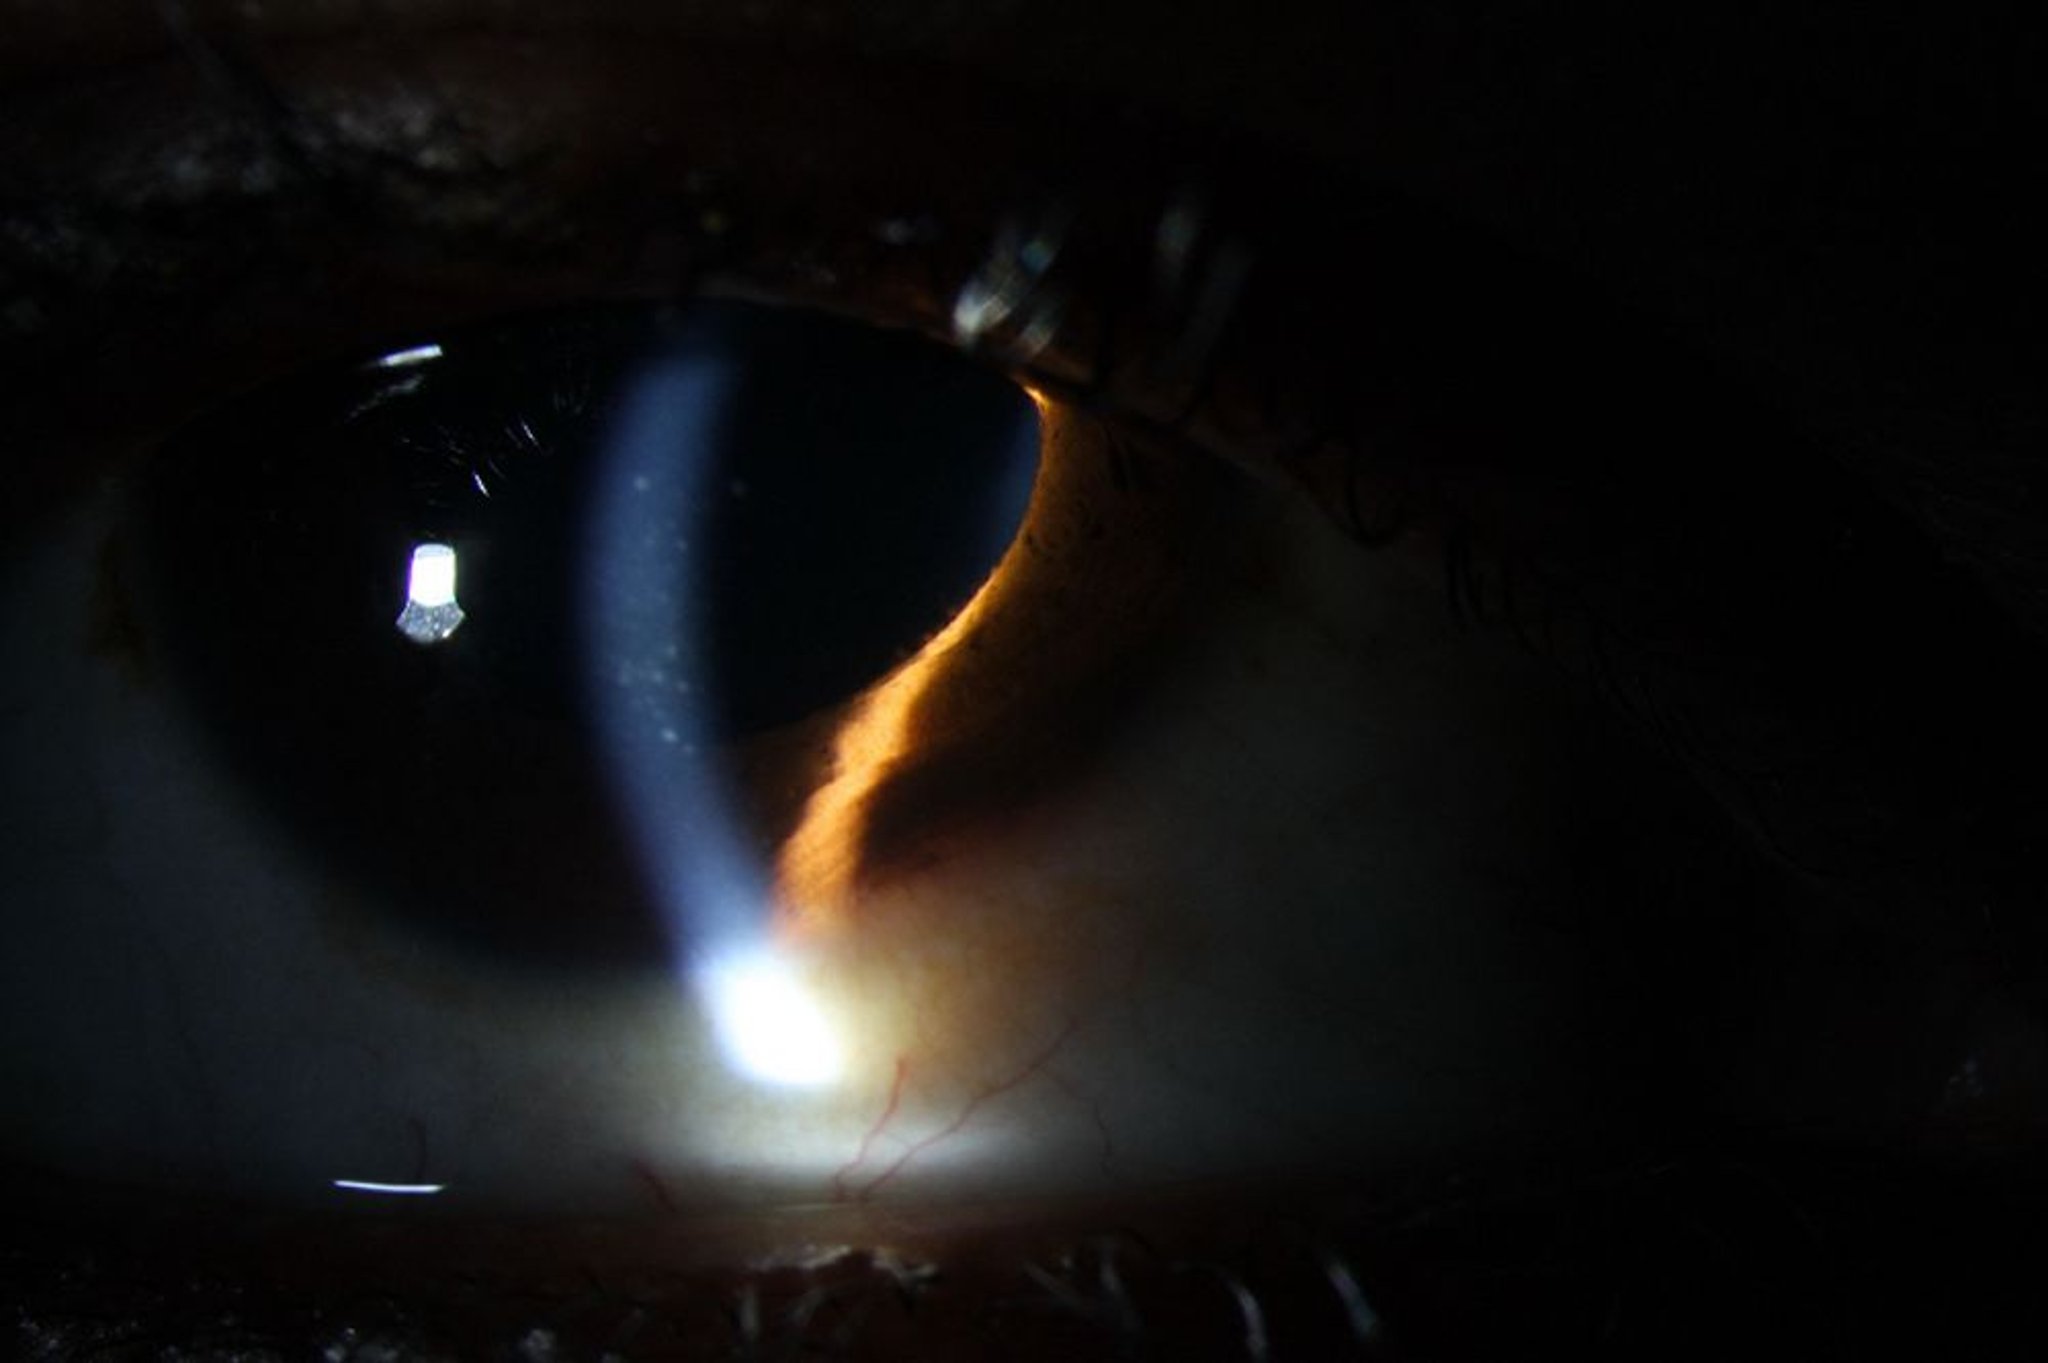

Увеит (передний)

Передний увеит может вызвать покраснение, преципитат кератина на эндотелии роговицы (видимый), также как и наличие лейкоцитов и воспаления (белка) в передней камере глаза.

Image courtesy of Sunir Garg, MD.